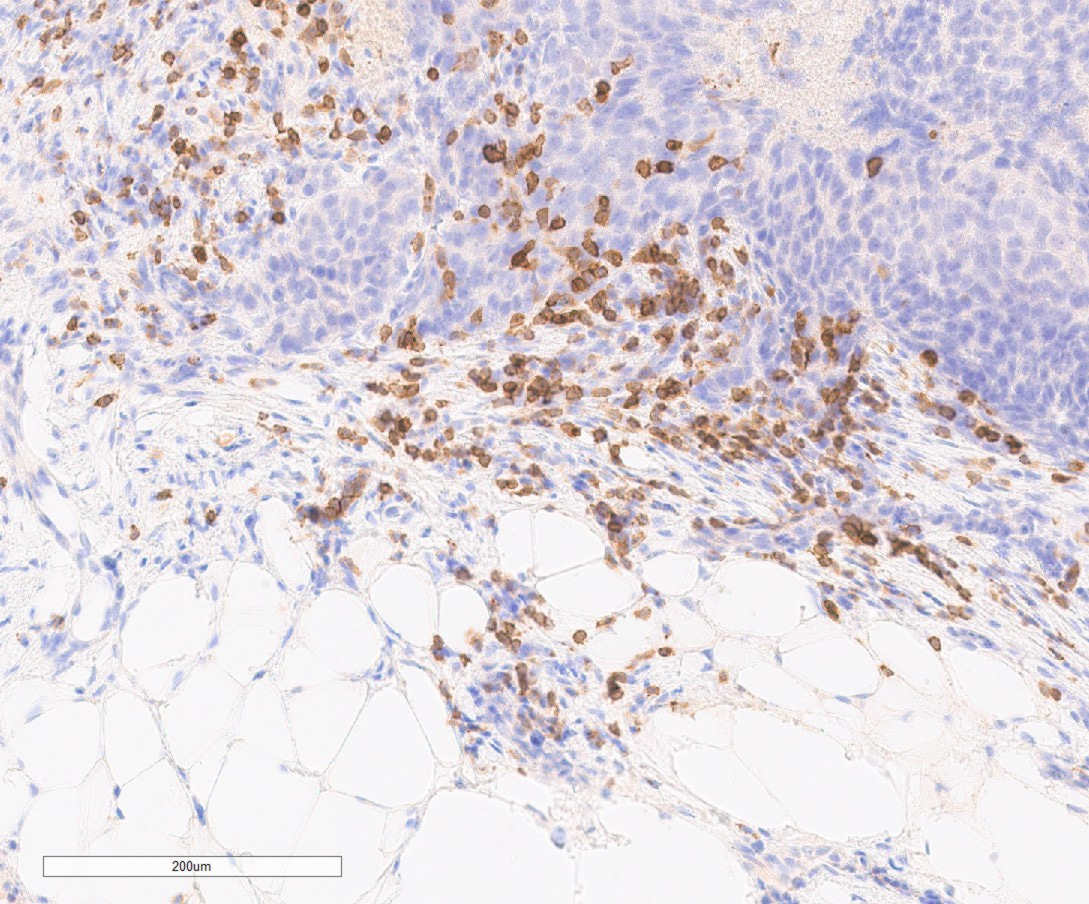

Histological section of ovarian cancer and adipose tissue

Immunohistochemical image (CD3 staining for T cells) of an ovarian cancer section with adipose cells in the lower part and tumor cells in the upper part with ample T cells sitting at the interface between the two compartments.